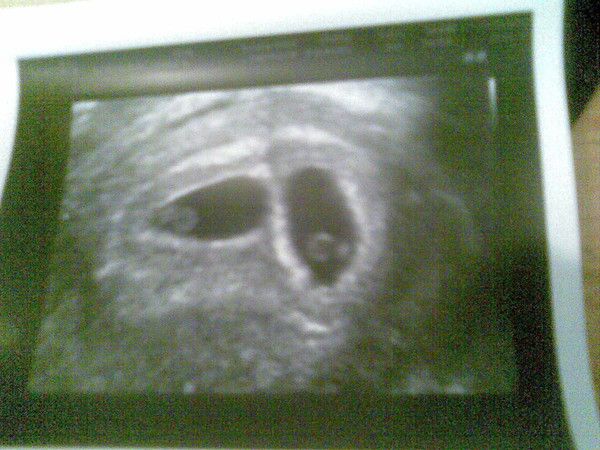

Meine Mäuse sind mit wöchiger verfrühung spontan zur Welt gekommen. Allerdings nach Einleitung.

Am 24.01.2012 war es dann endlich soweit.

Mia-Sophy kam um 10:55 uhr mit 43 cm und 1830gramm zur Welt. Ihre Schwester Lina-Josefine folgte ihr 6 min später mit 45 cm und 2190 gramm